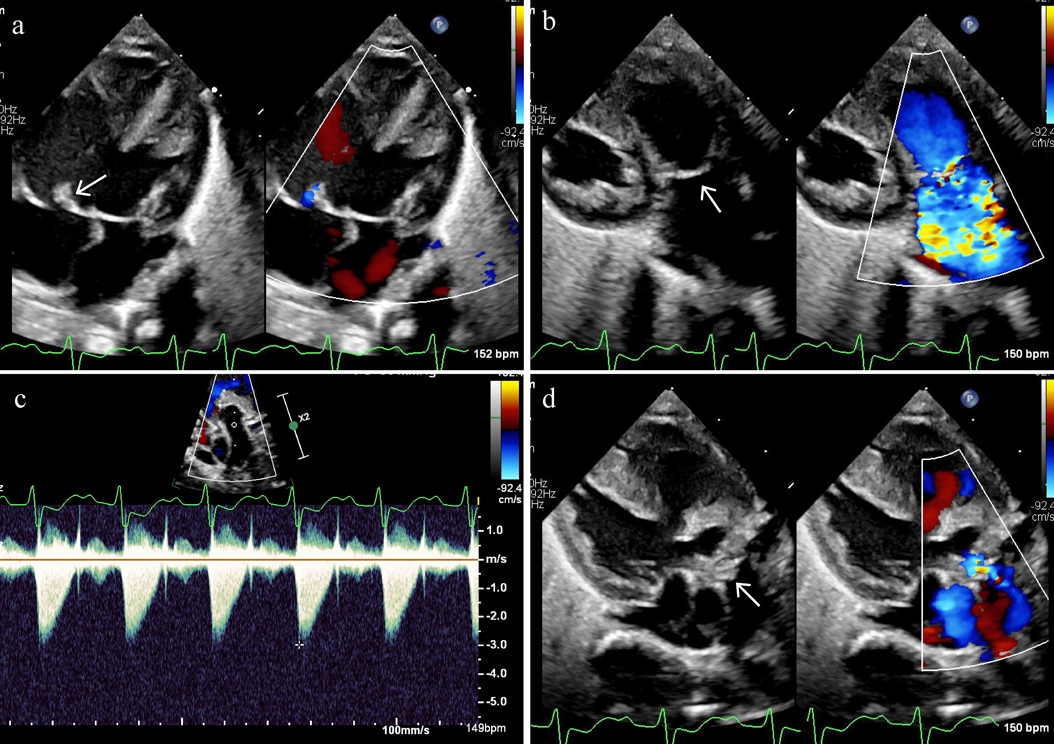

Fig. 1 Polyvalvular legions in a patient with trisomy 18

a) Hypertrophic septal leaflet of tricuspid valve (arrow). b) Thick and domed pulmonary valve (arrow). c) Continuous wave Doppler interrogation of pulmonary valve with peak velocity of 3.0 m/sec, suggesting moderate stenosis. d) Hypertrophic aortic valve (arrow).